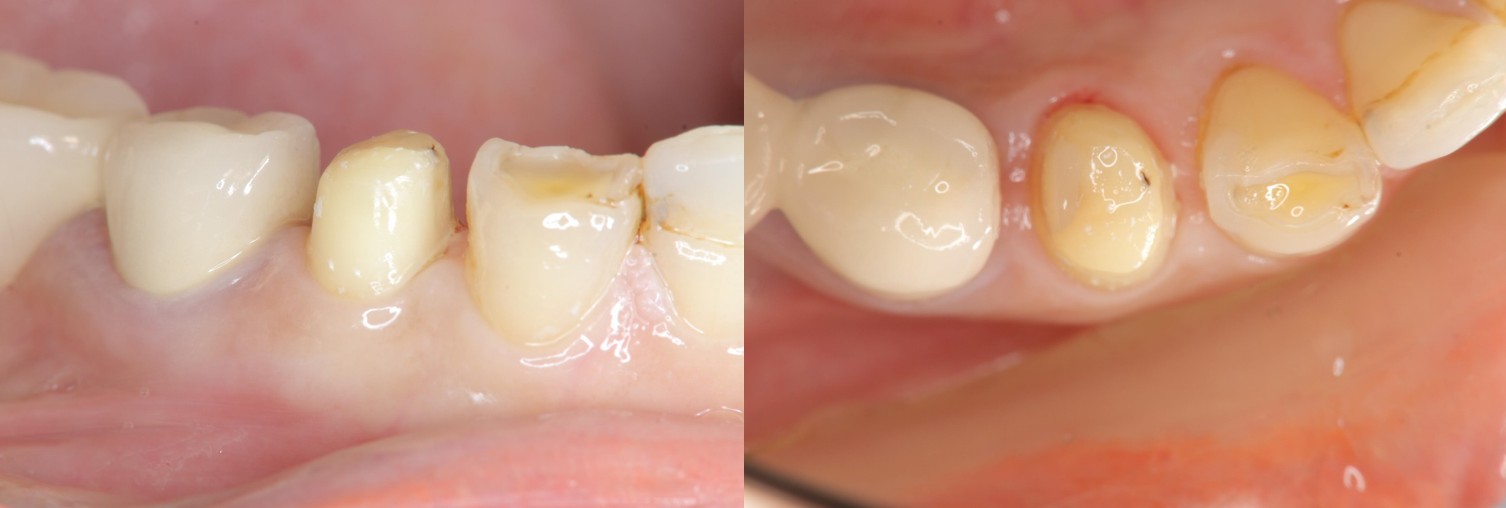

治療前,蛀牙卡食物

治療前,嚴重鄰接面蛀牙

牙齒製備